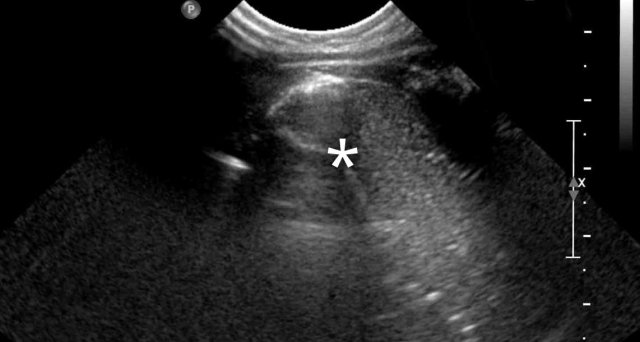

Image

Neonate, 39 weeks gestational age, antenatal suspicion of CPAM left lower lobe.

Radiograph shows a subtle, not well circumscribed lesion on the left lower lobe.

CT at age of one month shows a mixed lesion, both cystic and solid, with a large feeding artery from the descending aorta, in keeping with sequester.